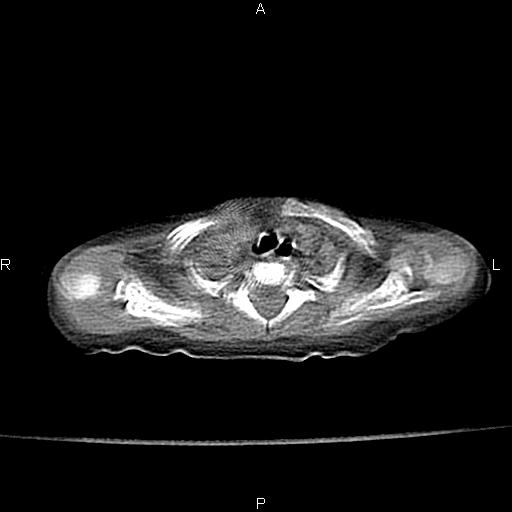

以下是引用aa13877358820在2010-7-26 12:35:00的发言:[br]男性,三个月,卧位胸片,咳嗽、气促、发热14天,两肺闻及细小水泡音。[br]